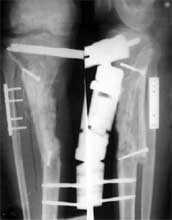

胫骨上段骨折术后1年,骨缺损、骨不连

异体皮质骨桥接骨缺损,异体松质骨与自体红骨髓复合后,填充入间隙中。

术后1年,骨折愈合